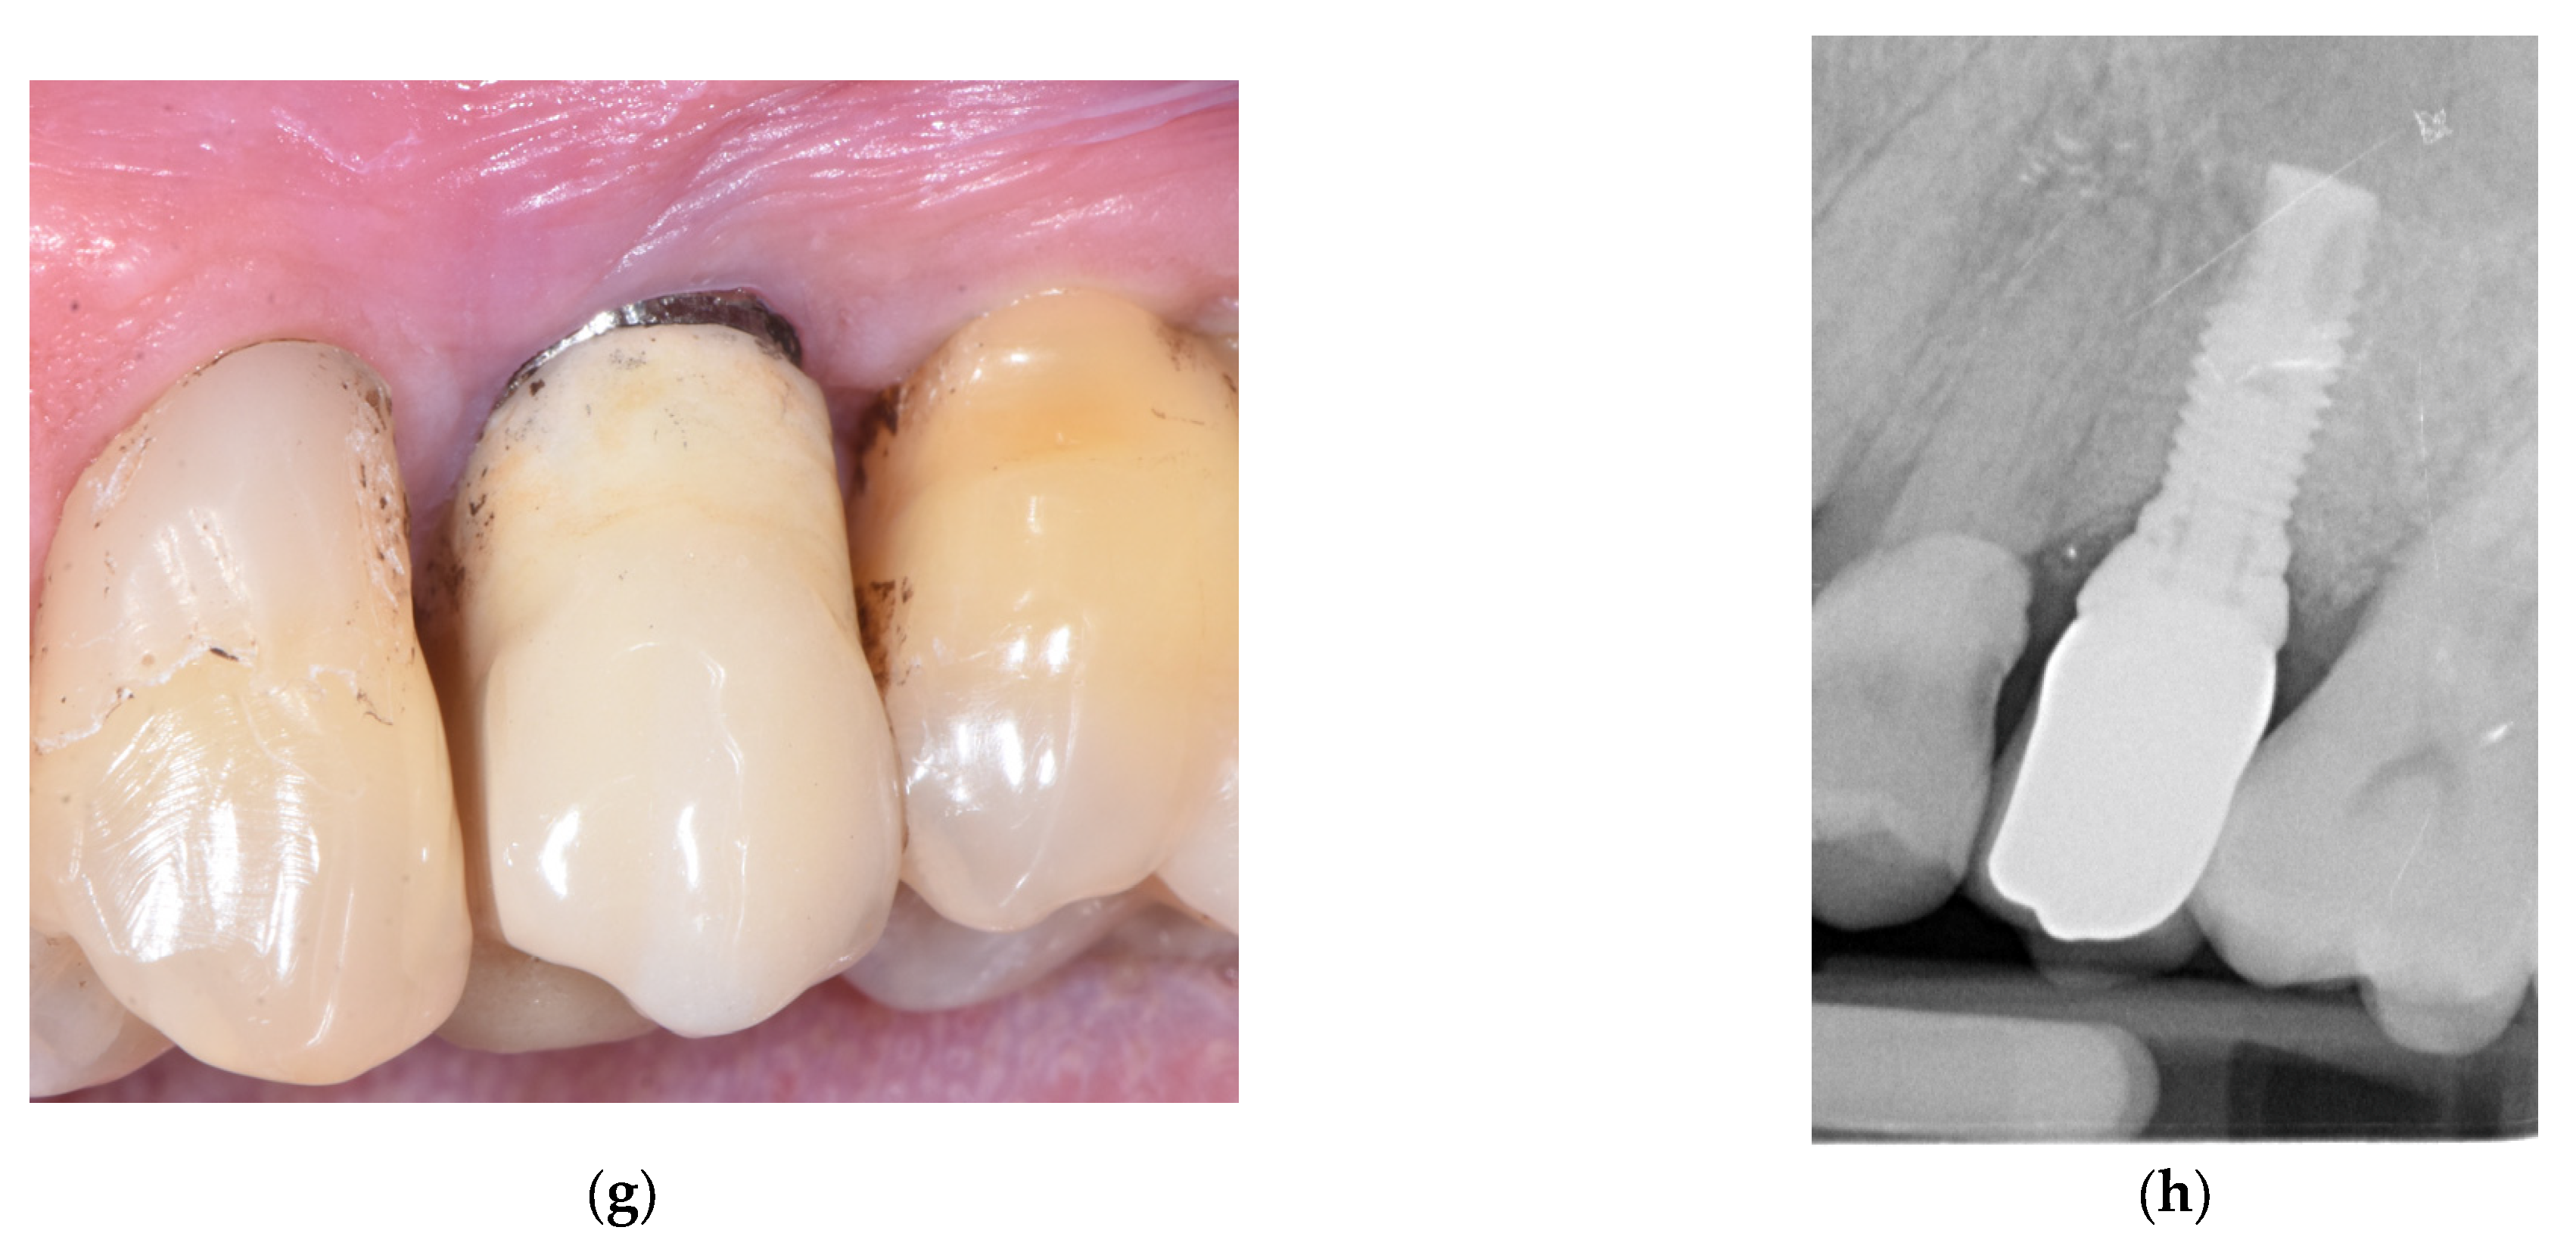

2. Materials and Methods

3. Results

- Bianchini, M.A.; Galarraga-Vinueza, M.E.; Bedoya, K.A.; Correa, B.B.; de Souza Magini, R.; Schwarz, F. Implantoplasty Enhancing Peri-implant Bone Stability Over a 3-Year Follow-up: A Case Series. Int. J. Periodontics Restor. Dent. 2020, 40, e1–e8. [Google Scholar] [CrossRef]

- Bianchini, M.A.; Galarraga-Vinueza, M.E.; Apaza-Bedoya, K.; De Souza, J.M.; Magini, R.; Schwarz, F. Two to six-year disease resolution and marginal bone stability rates of a modified resective-implantoplasty therapy in 32 peri-implantitis cases. Clin. Implant. Dent. Relat. Res. 2019, 21, 758–765. [Google Scholar] [CrossRef] [PubMed]